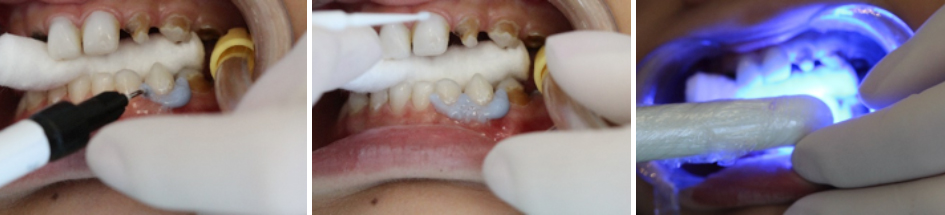

Em seguida realizou-se o isolamento relativo com rolete de algodão e secagem dos elementos com jato de ar. Foi realizada barreira gengival e fotopolimerização da mesma. (foto 7, 8 e 9)

Perfurou-se a cápsula prateada com o microaplicador prateado com movimentos circulares, aplicou-se o produto sobre as lesões por 60 segundos. (foto 10, 11)